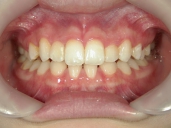

矯正歯科 治療後 正面